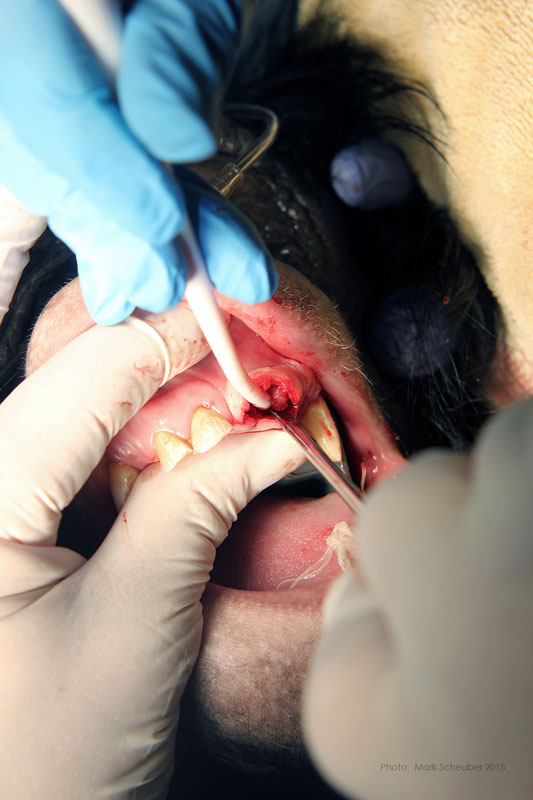

February, 2015Milwaukee County Zoo.Photos by Mark Scheuber, Zoo Keeper/Photographer

Maxillary left central incisor and lateral incisor residual roots. Region was inflamed, edematous prior to two weeks of antibiotic therapy.

Incision on crest of ridge.

556 surgical bur used to remove approximately 2mm. of alveolar bone surrounding each root ("ditching".)

Luxator technique utilized to remove residual roots.

Simple interrupted sutures placed with knots inside the wound so that Makanza will find it difficult to disturb them with his fingers and tongue.Rachel - Mongolian (Bactrian) Camel